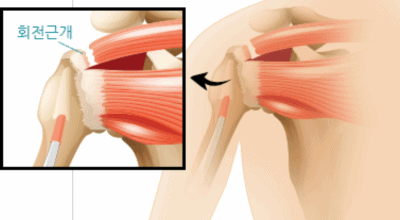

회전근개 증후군은 회전근개에 변형과 파열이 발생된 질환을 말합니다. 회전근개란 어깨와 팔을 연결하는 4개의 근육(극상근, 극하근, 소원근, 겹갑하근) 또는 힘줄로 이루어져 있는 것으로 보입니다. 어깨 근육통을 막연히 오십견으로 알고 방치하다가 치료 시기가 늦어지는 경우가 있습니다. 적절한 시기에 병원에 가는 것이 필요합니다.